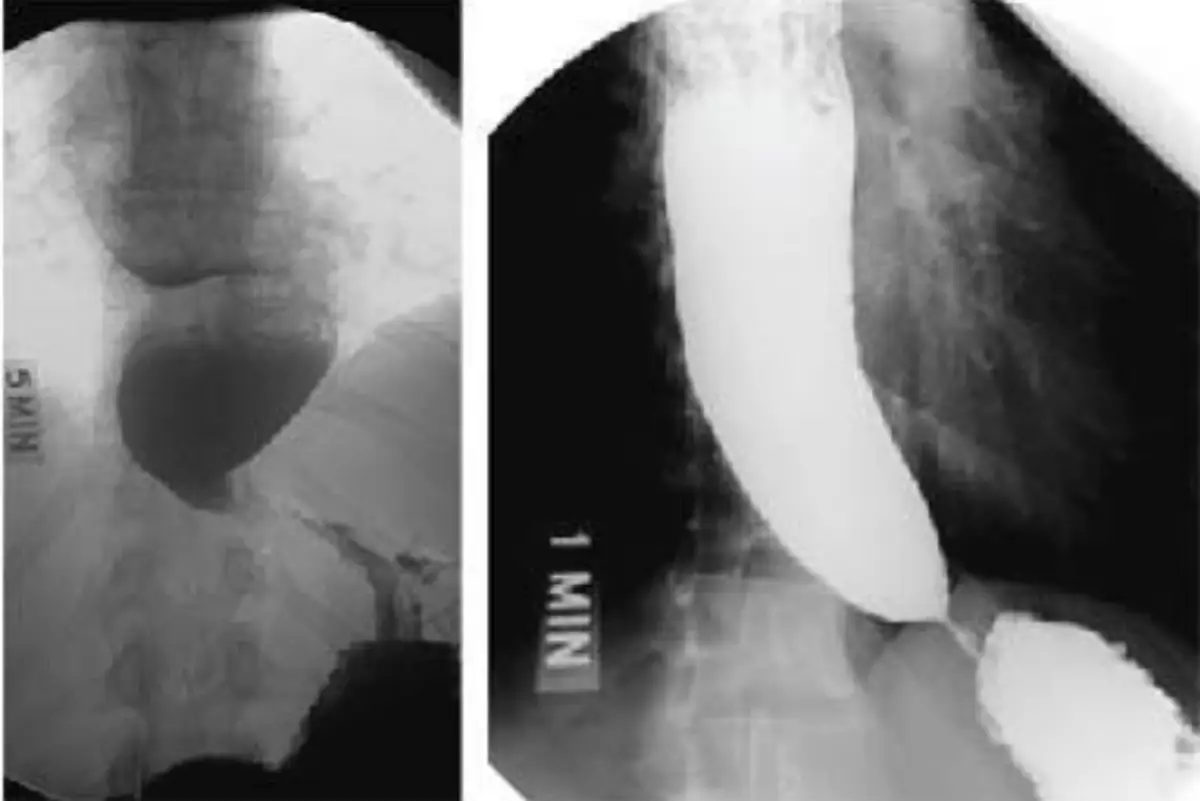

本題主軸在於食道動力障礙的鑑別:圖A呈現食道近端擴張伴下括約肌呈尖狀(bird’s-beak)狹窄,是典型的achalasia;圖B呈現多處非協調性收縮,形似rosary-beads或corkscrew,是diffuse esophageal spasm(DES)。

圖A(左側):鉍劑通過食道至胃端時,遠端食道呈對稱性錐狀狹窄(bird’s-beak),近端食道明顯擴張,停滯現象明顯,為achalasia最典型表現。

圖A(右側):可能為同一病人延遲影像,可見近端食道擴張仍然積留造影劑,進一步支持括約肌鬆弛不全。